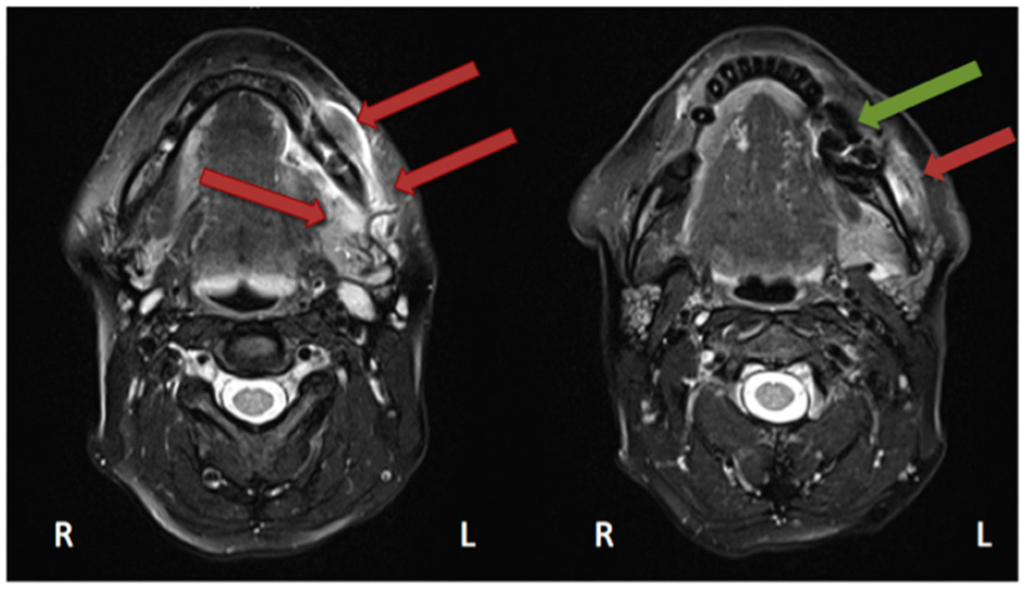

In the study by Guggenberger et al., all MRONJ foci “showed markedly decreased signal on T1-with increased signal on T2-weighted images” [29]. This was the case for all except one patient, in whom an intermediate signal on T2 was seen. “Contrast uptake of affected bone and surrounding tissue was noted in all patients and foci of BONJ” [29]. Furthermore, the authors described that contrast-enhanced MR imaging shows more extensive changes in comparison with the clinical examination and CBCT imaging [29]. In their study, Stockmann et al. stated that “MRI has a high detectability for BONJ lesions” [18] but limitations were found concerning the extent of the detection [18]. Bedogni et al. assessed in their study 11 MRI scans performed on MRONJ patients [42]. Gadolinium (intravenous) was used as a contrast agent. These images showed two patterns of bone disease: “Exposed areas showed a low signal in T1- and T2-weighted and inversion recovery images, which suggests low water content and is histopathologically correlated with paucity in cells and vessels (osteonecrotic pattern). Unexposed diseased bone was characterised by T1 hypointensity and T2 and IR hyperintensity, which suggests high water content and inflammation, associated with hypercellularity, osteogenesis, and hypervascularity (osteomyelitic pattern).” [42]. Hypointensity in T1 was also seen in MRI scans performed on our patient (Figure 6 and Figure 7).

Figure 6.

Magnetic resonance imaging (Siemens, Avanto, 1.5T, Sequence: T1 tse tra) Patient: 48 years old, female, metastatic breast cancer, zoledronic acid for 2 years (panoramic radiograph Figure 1). Green arrow showing the MRONJ necrosis, red arrows showing the oedema, blue arrows showing the differences between the right side: normal fatty bone marrow and left side: signal loss, due to loss of fat. Pair of screenshots. AAMOS staging: stage 2.

Figure 7.

Magnetic resonance imaging (Siemens, Avanto, 1.5T, Sequence: T2 tse tra) Patient: 48 years old, female, metastatic breast cancer, zoledronic acid for 2 years (panoramic radiograph Figure 1). Green arrow showing the MRONJ necrosis: hypointense bone marrow, red arrows showing the oedema. Pair of screenshots. AAMOS staging: stage 2.

Krishnan et al. described early MRI findings of MRONJ in their publication. This includes at the early stage “the loss of the normal T1 hyperintensity of fatty marrow in the mandible and maxilla.” [43] “Bone destruction, soft tissue edema and enhancement, inferior alveolar nerve thickening, and pterygoid muscle swelling and enhancement” [43] are findings of more advanced stages. Exemplary MRI protocols are found in the publications by Bedogni et al., Stockmann et al. or García-Ferrer et al. [18,42,44]. Although MRI scans are very helpful for defining the extent, the 99Tcm-MDP 3-phase bone scan was superior to both CT and MRI [45].